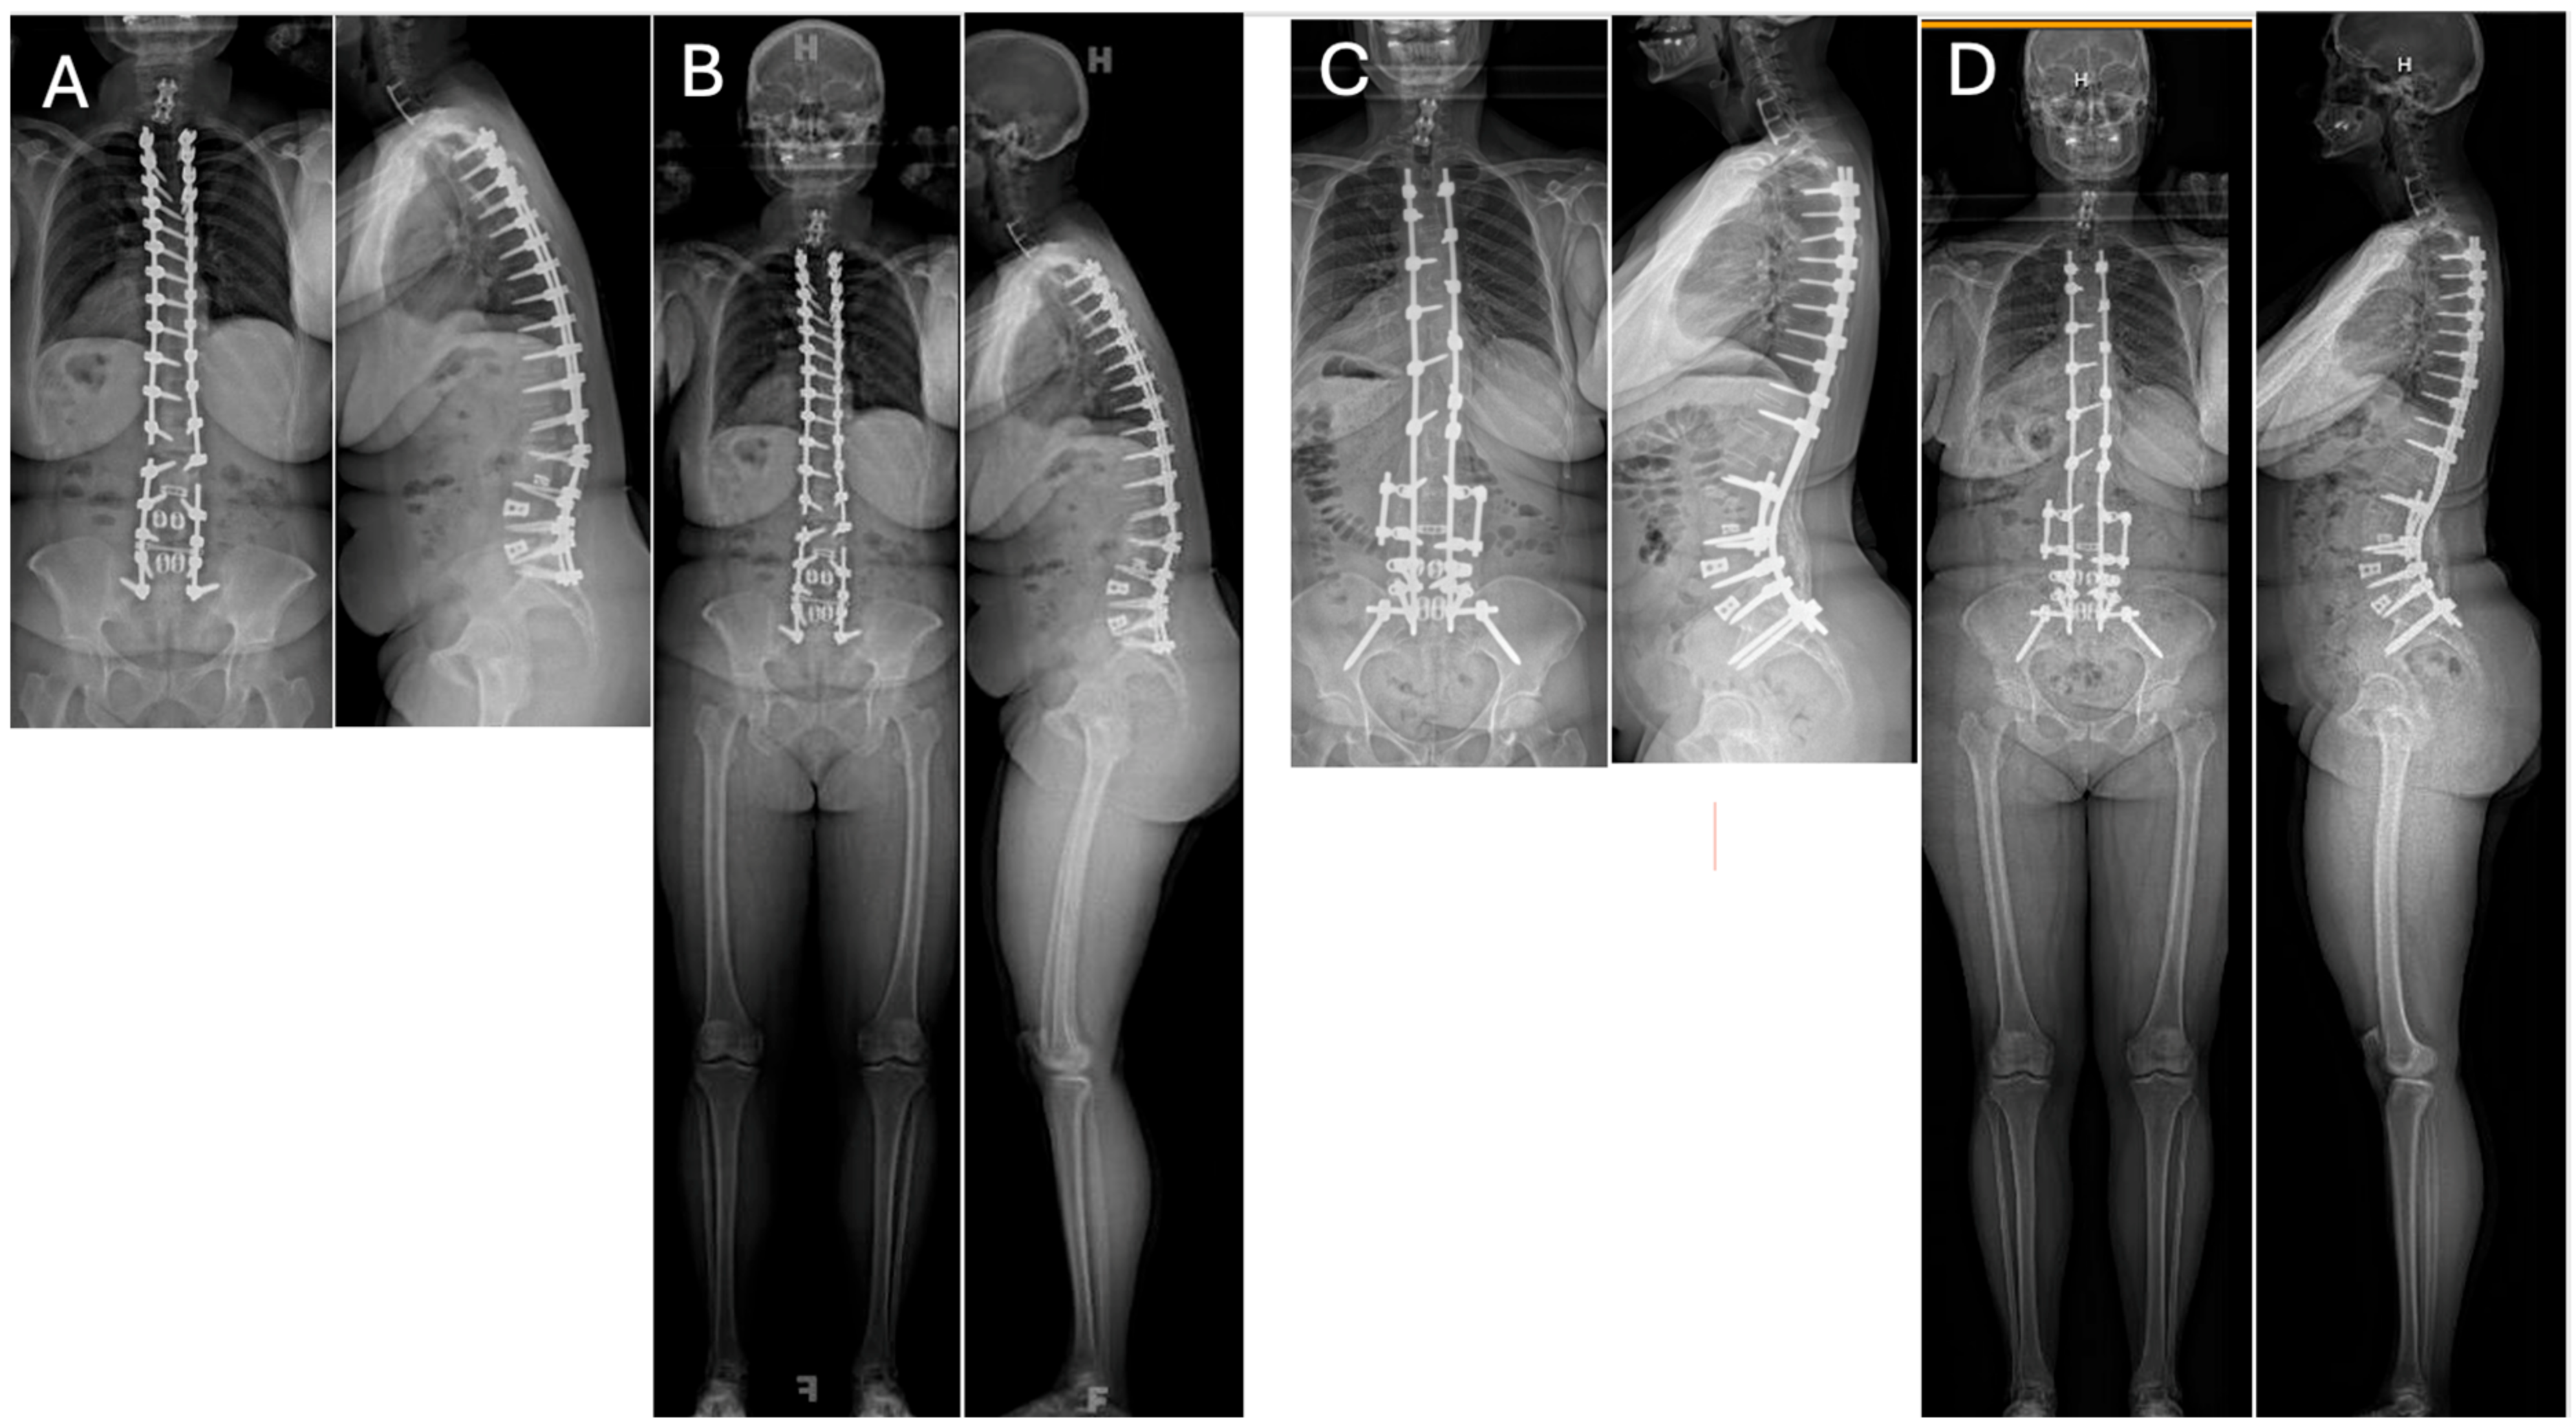

Pre-operatively, full-length standing radiographs should be obtained to evaluate sagittal parameters. A CT scan should be obtained to evaluate for pseudarthrosis or screw loosening not apparent on radiographic imaging. In patients with pseudarthrosis and maintained correction, revision arthrodesis with or without interbody fusion, along with the upsizing of any loose pedicle screws and rod replacement may be considered [23]. In patients with pseudarthrosis and persistent or recurrent sagittal malalignment, additional correction should be obtained with interbody cages and/or posterior-based osteotomies depending on the amount of correction required (Figure 1). Subsequent rod replacement with or without the placement of accessory or satellite rods can then be performed.

Figure 1.

36″ (A) and EOS (B) Postero-Anterior (PA) and lateral radiographs of a 49-year-old female who had a previous posterior spinal fusion from T3 to the pelvis which failed with broken instrumentation and pseudoarthrosis. The patient fell forward in the sagittal plane resulting in sagittal decompensation and malalignment causing debilitating pain. 36″ (C) and EOS (D) PA and Lateral radiographs 3 years post-operatively from the removal of instrumentation, revision T3-Pelvis posterior spinal fusion with quarter-inch stainless steel rods and pedicle subtraction osteotomy (PSO) at L3 using the satellite rod configuration at the PSO site.